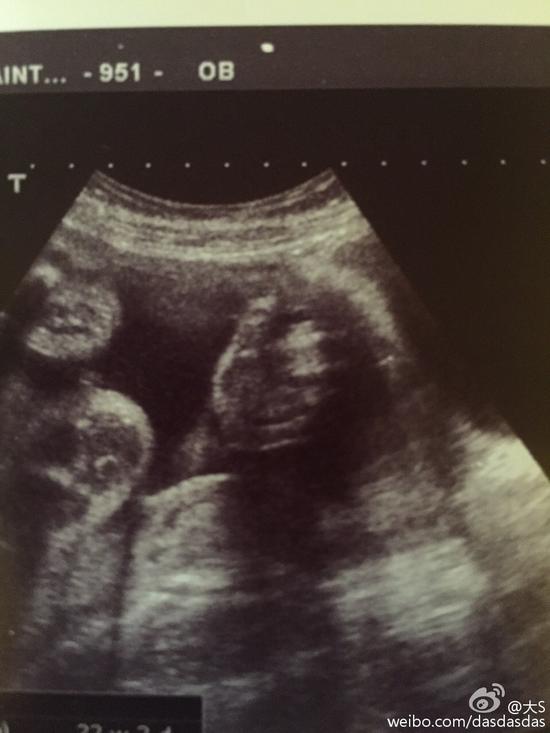

大S二胎B超照大S二胎B超照

照片中,大S和汪小菲依偎在一起,由于拍摄角度奇特,隆起的肚子比大S和汪小菲的脸都大,网友调侃:“肚子好大,像是怀了双胞胎。”第二张baby的B超照,依稀看出婴儿的轮廓,仿佛伸出手指点赞。